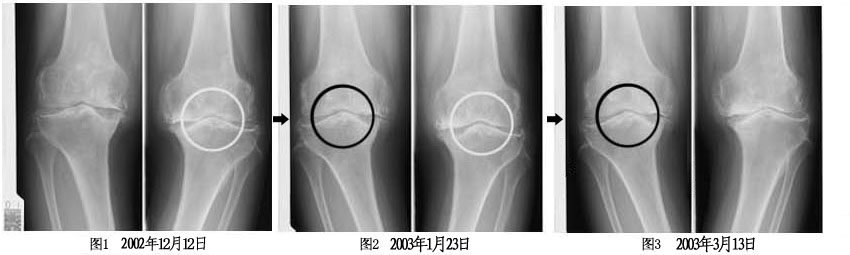

津田女士自1973年以来,患有30多年的退行性关节炎。2002年12月12日,因两膝关节痛,到本院接受诊疗。初诊时,因已接受过整形外科, 接骨院, 按摩等各种治疗,2002年12月经过患者本人同意,不用抗炎药物,而开始以每日给予7.5g 百傲鲨锯峰齿鲛软骨粉末的方式治疗。

经过一个月后,根据X光片检查,确认骨头与骨头间已产生间隙(请参见图二)。在那之后的十三周后,能确认骨头和骨头间持续产生间隙(请参见图三),即确认到软骨再生。

通常像这样的患者,原本会持续恶化下去,而整型外科医生也会建议患者接受「人工关节置换手术」。站在医学角度上思考,虽然软骨再生实在令人难以置信,但事实上,透过X光片检查,证实其的确具有软骨再生作用。

以上的临床结果,百傲鲨锯峰齿鲛软骨粉末具有镇痛效果,也可对改善QOL(生活质量)赋予期待。另外,从确认软骨间隙能够增大一事,也可得知其具有软骨再生效果。